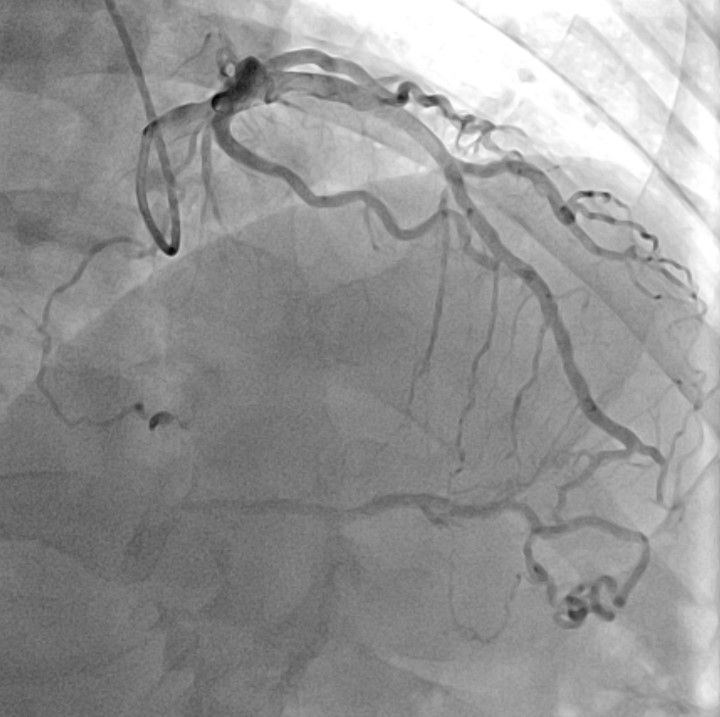

Diagnostic coronary angiography revealed a very long (>40mm) chronic total occlusion of the RCA with a J-CTO score >3. The lesion presented with ambiguous caps at both the proximal entry and distal exit points. Well-developed septal collaterals supplying the posterior descending artery (PDA) were present (CC score 3). The distal vessel architecture was further complicated by in-stent restenosis (ISR) from the previous stent implantation.

The procedure began with an antegrade attempt using a Sion wire in Corsair Pro, which failed due to the ambiguous proximal cap. We promptly switched to a retrograde approach via the septal channels. A SUOH 03 wire successfully surfed the collaterals to the distal RCA but was unable to penetrate the distal ISR segment. To bypass this barrier, we escalated to a Gladius polymer wire, which passed the ISR but tracked into the false lumen, causing a retrograde dissection. We exchanged for a Gaia Next 2 wire and carefully redirected the tip to puncture back into the true lumen near the proximal cap. Despite successful wiring, the retrograde microcatheter could not cross the calcified proximal cap to allow for externalization. To resolve this, we employed the "Tip-In" technique: an antegrade microcatheter was advanced to the tip of the retrograde wire inside the guiding catheter, and the retrograde wire was steered into the antegrade catheter to secure the rail. Following this, we exchanged for a Rota wire. Rotational Atherectomy with a 1.25mm burr was performed to modify the severe proximal calcified nodule that had prevented microcatheter passage. After IVUS-confirmed plaque modification, we implanted two overlapping Xience Skypoint stents (4.0 x 48 mm) and performed high-pressure post-dilatation with a 4.5mm non-compliant balloon.